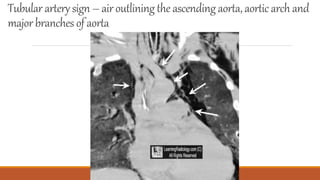

Tubular artery sign

Tubulararterysign – airoutliningthe ascendingaorta,aorticarchand

majorbranches of aorta

Tubulararterysign – airoutliningtheascendingaorta,aorticarchand majorbranches of aorta